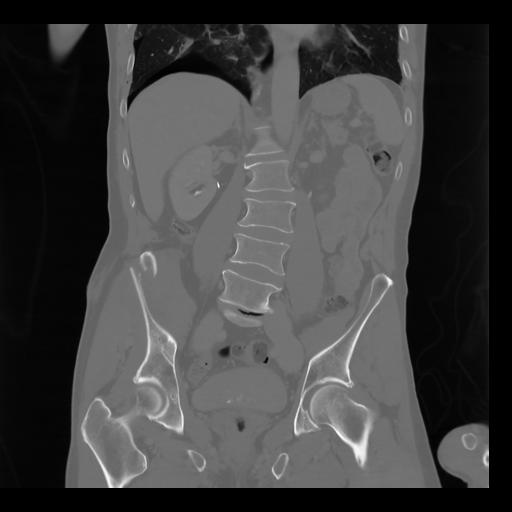

35 CUERPO,CE,Coronal,3.000,CUERPO,Coronal,